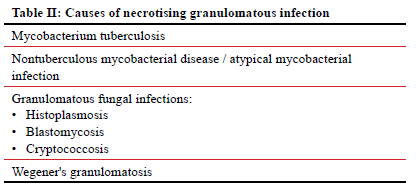

One needs to be mindful that TB is not the only condition that can lead to granulomatous inflammation, as represented in Table I.43 The definitive histological hallmark for diagnosing TB is the presence of necrotising granulomas. However, the absence of necrotising granulomas does not preclude the diagnosis of breast TB, and TB often presents with a combination of necrotising and non-necrotising granulomas influenced by the inflammatory process. Additionally, a small biopsy sample size can result in the non-visualisation of necrotising granulomas.44 Other pathologies, such as infections with non-tuberculous mycobacteria, Wegener's granulomatosis, and granulomatous fungal infections, can also produce necrotising granulomas in breast tissue, as represented in Table II.45 Despite the relatively lower prevalence of granulomatous breast fungal infections compared to breast TB, it is imperative to exclude these conditions, especially in patients with relevant histories, immunodeficiencies, or those residing in endemic regions.45,46 In non-endemic TB areas, the most common causes of granulomatous inflammation of the breast include silicone granuloma, fat necrosis, and idiopathic granulomatous mastitis.46 Tailoring investigative approaches based on patient history, physical exam, and geographical region is crucial, as certain diagnostic tests may be unnecessary in specific contexts. This approach ensures a more efficient and accurate diagnostic process, avoiding redundant or irrelevant investigations. Figure 5 illustrates a proposed diagnostic pathway for breast TB, emphasising the inclusion of serological tests, such as serum ANCA, ACE, and rheumatoid factor, to exclude alternative diagnoses before initiating TB treatment.